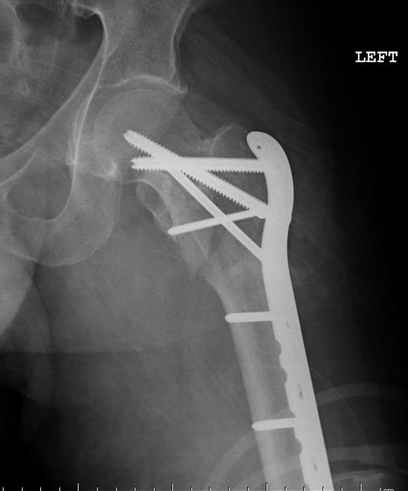

Re: [1/3] Перелом проксимального бедра

Применили проксимальную Synthes Locking plate, из-за множественных фрагментов посчитали более приемлемым в этом случае (клиника университетская, резиденты должны имет возможность созерцать разные варианты остеосинтеза).

Также старался минимизировать доступ на уровне перелома с субвастус доступом, диафиз фиксирован перкутанно, не стали гонятся за малым вертелом, как смог зафиксировал.

Перелом из четырех фрагментов, не стабильный (лекция Michael R. Baumgaertner, http://www.hwbf.org/ota/bfc/baumg/exp.htm), нужна стабильная фиксация.

Фиксация таких нестабильных чрезвертельных и reverse obliquity субтрохантерик переломов всегда была сложной задачей и ранее использовали Blade Plate. Но многие локальные общие ортопеды, к которым, в основном поступают такие больные, имели трудности с применением импланта, где необходимо было точная калькуляция по введению Blade и поэтому Synthes разработал Proximal Locking plate как альтернативу, где три проксимальные шурупа в разных направлениях создают концепцию угловой стабильности Blade Plate.

Со второго дня движения в суставе, контрольный осмотр через две недели и в зависимости от рентгенологического сращения, дозированную нагрузку с постепенным увеличением начнем через 5-6 недель.